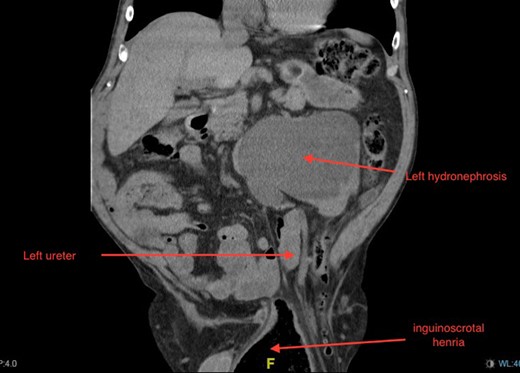

Non-contrast CT of the chest, abdomen and pelvis was performed on admission looking for malignancy considering his visible haematuria and significant unintentional weight loss. This demonstrated severe bilateral hydronephrosis and hydroureter, which was more prominent on the left side (Figs 2–4). The left ureter tapered in the pelvis and neither the bladder nor either ureter was seen in the inguinal canal and a large, left-sided inguinoscrotal hernia was seen containing distal colon. Bilateral loss of renal cortical thickness, a potassium of 6.0 mmol/L and an eGFR of 9 mL/min was suggestive of chronically obstructed kidneys.

Coronal section of CT demonstrating severe left-sided hydronephrosis and left ureter compressed distally by hernia. Left distal ureter is closely related to neck of hernia sac at the deep ring.